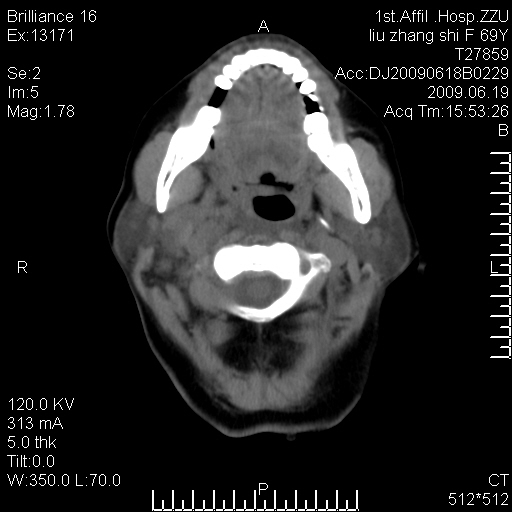

标题: CT26782:女,69岁,颈部占位,3天后公布病理结果。

【病理证实系列】女,69岁,颈部占位,有病理结果,3天后公布。(由于病例时间较久,临床资料不全,请网友见谅)本系列将有几百种常见、少见及罕见病例,均经病理证实。病例资料来自郑州大学第一附属医院。与网友共享,本人有空就发。

甲状腺癌并颈部淋巴结转移。感谢楼主的良苦用心,谢谢。

甲状腺癌并颈部淋巴结转移。

需与鼻咽癌鉴别!

支持甲状腺癌广泛侵及周围结构并颈部淋巴结转移。

鉴别:淋巴瘤、恶性神经源性病变、恶性纤维组织细胞瘤。

病理结果:颈部非霍奇金淋巴瘤。